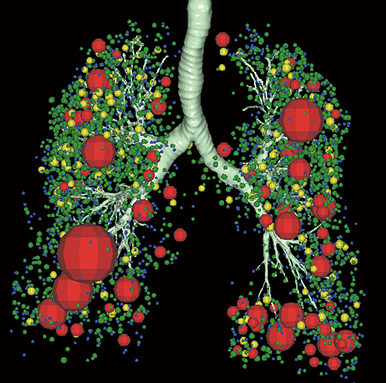

CT・MRIなどの断層画像から高精度な3D画像を描出し、解析を行う3D画像解析システム「SYNAPSE VINCENT Core」が、メディカルIT技術ブランド「REiLI(レイリ)」によるDeep Learningによって、さらなるバージョンアップを遂げました。膨大に蓄積された医用画像データを生かし、CTデータからの自動抽出機能や、脈管系の抽出機能が充実。画像認識技術を生かして、チーム医療を支え続けてきた富士フイルムだからこそ実現できた、AI時代の3D解析技術です。富士フイルムの「REiLI」が、チーム医療の最前線へと導きます。

「REiLI」によるDeep Learningを用いた臓器抽出で画像処理を簡単に行うことが可能です。

肺葉

肺解析